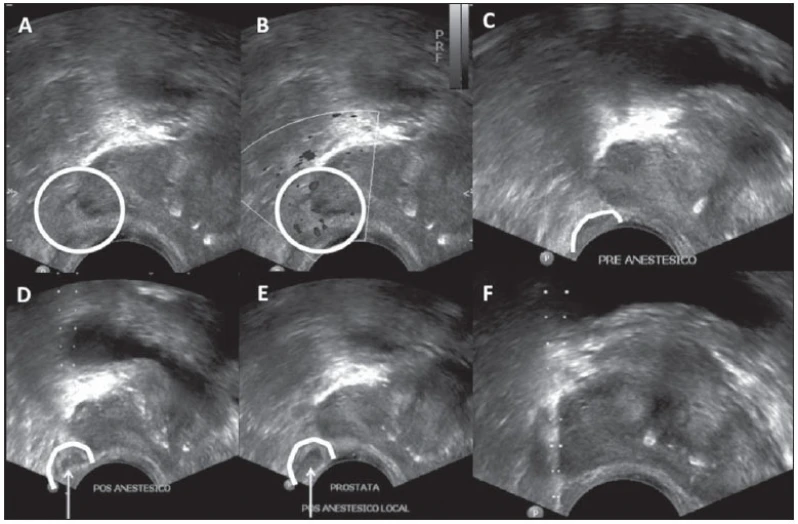

A urologia é uma especialidade da medicina que trata problemas do sistema urinário masculino e feminino, tratando também do sistema reprodutor masculino. Para quem busca por biopsia de próstata em São Paulo no Parque do Carmo, a DK Urologistas é uma empresa qualificada para realizar esse exame para você. Para manter a saúde em dia é imprescindível realizar consultas periódicas ao médico para que seja feita uma avaliação.

Quer saber mais sobre biopsia de próstata em São Paulo no Parque do Carmo? Encontre a solução que você precisa aqui na DK Urologistas. São diversas opções disponibilizadas, como urologistas, biopsia de próstata, vasectomia, cirurgias de fimose, disfunção erétil, ejaculação precoce e estudo urodinâmico. Para tal sucesso, a empresa investiu em profissionais competentes e em equipamentos inovadores.